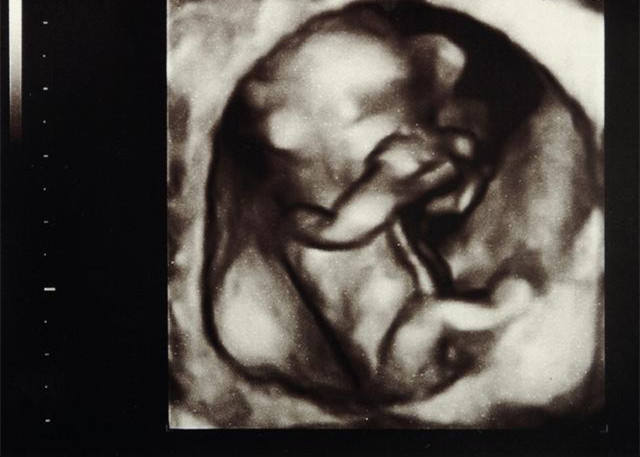

虽说精子和卵子是在输卵管里相遇、结合,但是他们形成受精卵之后,又会游回到子宫里,然后慢慢安家落户。所以只要是正常的妊娠,胎儿的发育都是在子宫里完成的。憋尿的时候,就能感受的到膀胱的位置,而子宫就在膀胱下面再深一点的位置。或者也可以说就是胎儿是在子宫里的,而子宫又在小肚子里,因此,胎儿也是在小肚子里。对生物有所了解的孕妇应该清楚,子宫是深藏在骨盆里的,而子宫的大小差不多像鸭梨那样大。在怀孕3个月的时候,胎儿也就只有几厘米长,虽说子宫在不断增大,但是还摸不到的,不过就超出骨盆一点点而已。

正常情况:在怀孕3个月末,子宫底约在耻骨联合上缘以上2--3横直,4个月末,脐与耻骨联合缘以之间,5个月末宫底在脐带下一分指,6个月末,子宫底在脐带上一横指,7个月末,子宫底在脐带以上三横直,妊娠到8个月末,子宫底在脐带与剑突之间,9个月末,子宫底最高,其中中央部位在剑突下二横直,两侧正好在缘下。异常情况:若连续2~3周宫底高度无变化,或宫高明显低于怀孕月份,应及时到医院查找病因。如果过分高于怀孕月份也应到医院检查,以排除羊水过多、滋养细胞疾病等,还可了解是否有多胎妊娠。